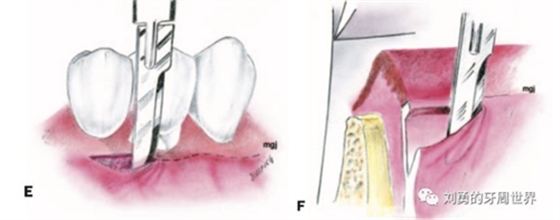

3、用15號刀片,在受區(qū)膜齦聯(lián)合的位置從遠(yuǎn)中向近中做半厚切口,刀片平行于骨面(E和F)

4、刀片按照受區(qū)的近遠(yuǎn)中長度完成初始的半厚瓣全長切口

5、刀片向根向繼續(xù)分離半厚瓣,冠根向延伸6-8mm,注意避讓頦神經(jīng),翻開半厚瓣如下圖: